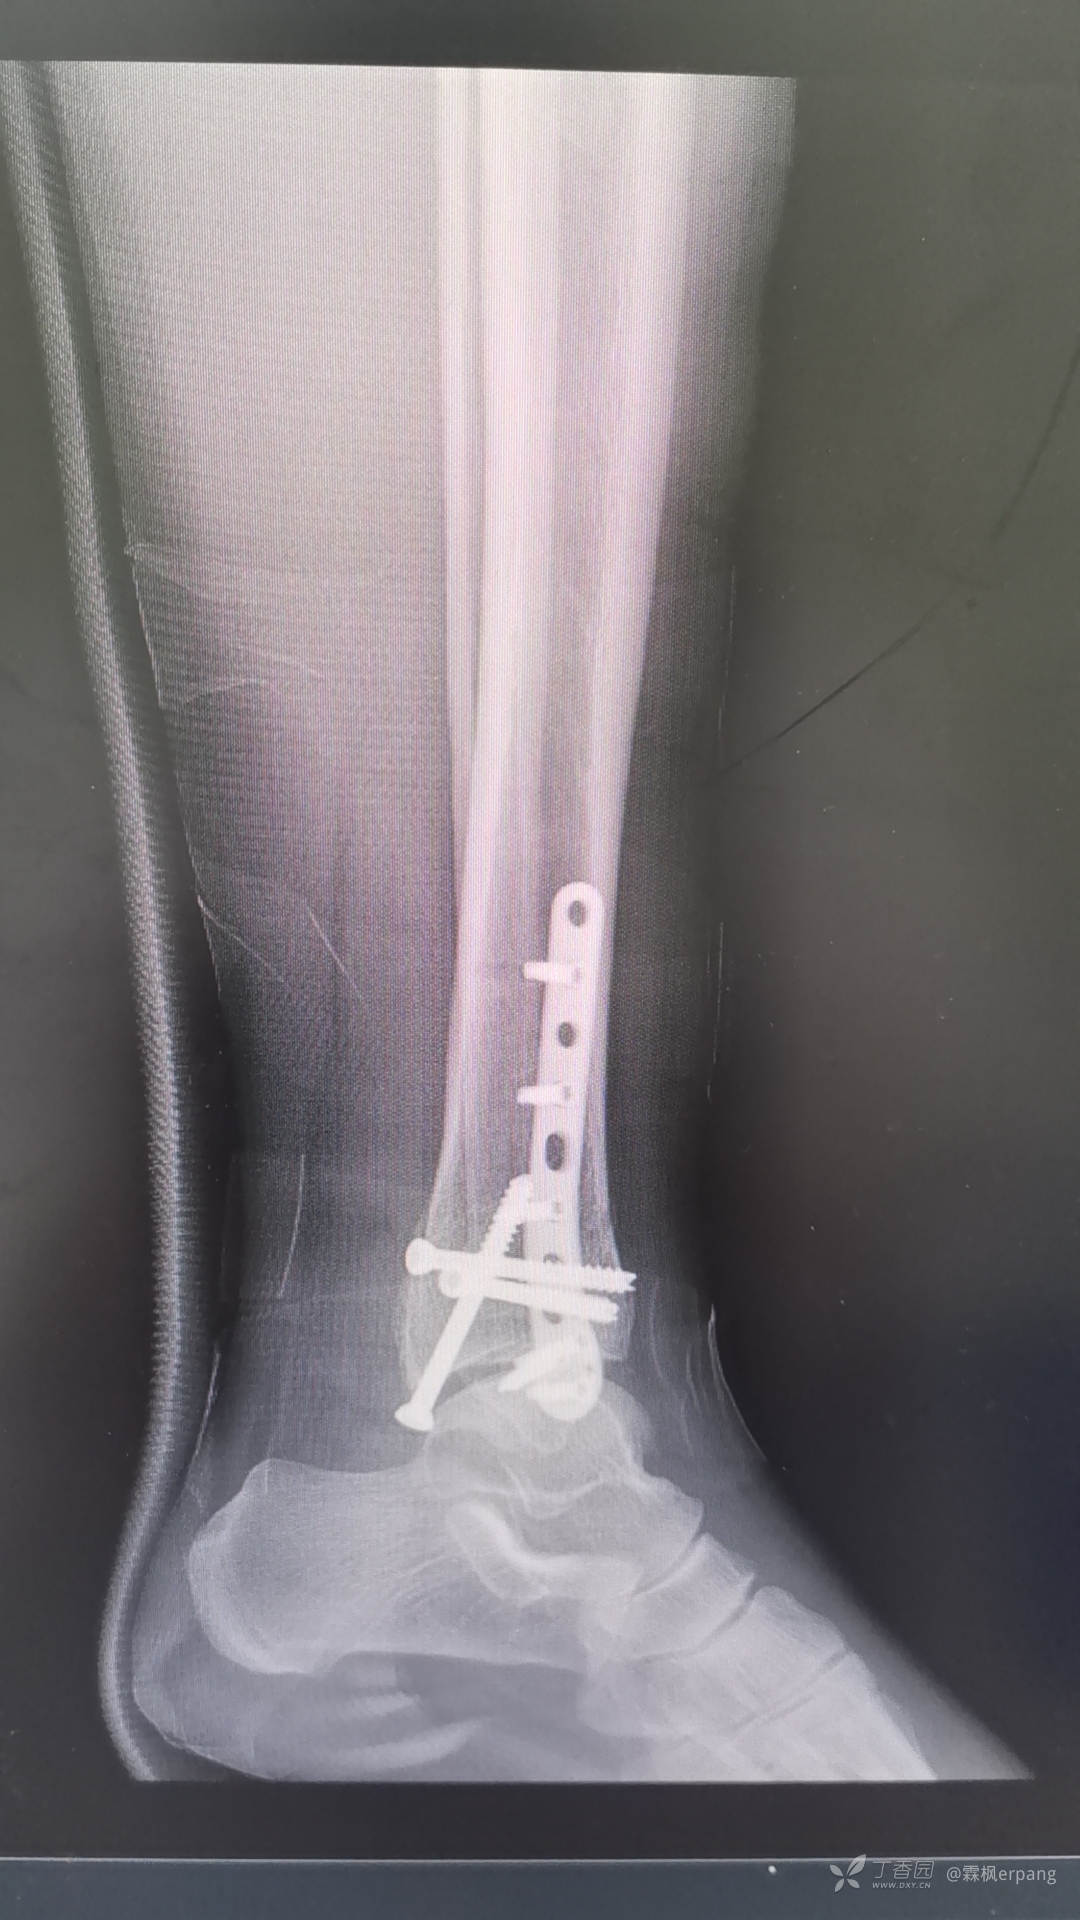

手术计划:后外侧切口做外踝和后踝,内侧闭合空心钉内固定。

术中钢板近端略偏前,无碍大局,未做调整。

术后片